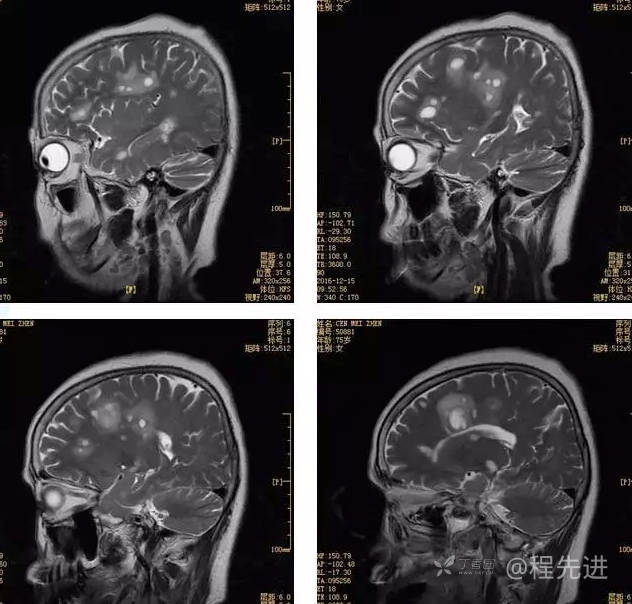

3月特别精彩病例|头晕伴左侧肢体乏力、行走不稳1周【结果已公布】

患者性别:女

患者年龄:75岁

简要病史:头晕伴左侧肢体乏力、行走不稳1周。否认高血压、脑梗塞、肝炎、糖尿病、肺结核病史。否认疫区疫水接触史。